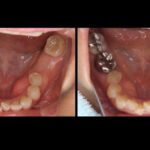

歯がボロボロでも治療できますか!? [bgRed] ☑歯がボロボロでこの先、自分の歯がどうなってしまうのか心配でたまらな...

上あごの骨が少なくインプラントが難しい場合 「骨が少ないので、インプラントは難しいかもしれませんね・・・」 そんな場合で...